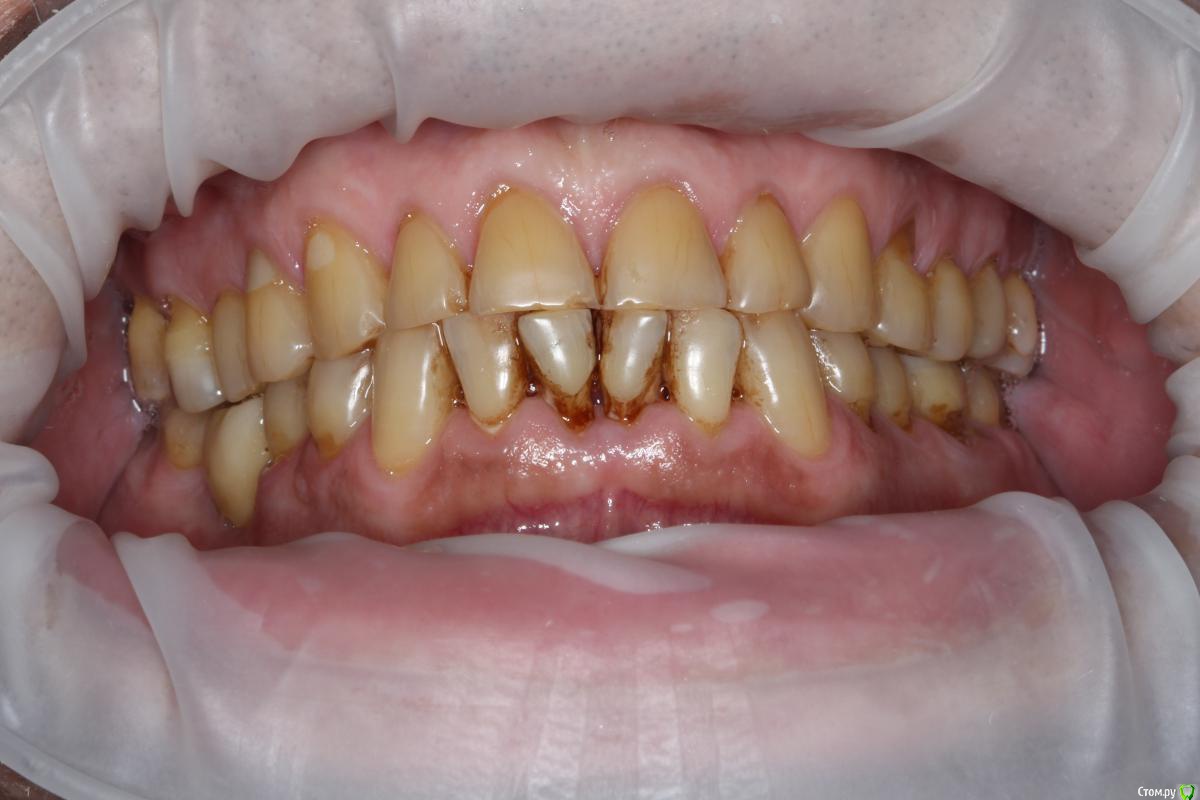

Robinbobin Опубликовано 27 марта, 2015 Поделиться Опубликовано 27 марта, 2015 (изменено) Пациент 57 лет с жалобами на стираемость зубов,чувствительность и бруксизм Хотелось бы услышать ваше мнение!!!! Изменено 27 марта, 2015 пользователем Robinbobin Ссылка на комментарий

Евгений Ходыкин Опубликовано 27 марта, 2015 Поделиться Опубликовано 27 марта, 2015 1) Стабилизировать пародонт.2) Закрытие рецессий, где это возможно.3) Вакс + мокап.4) Временный тотал.5) Постоянный тотал. 1 Ссылка на комментарий

Robinbobin Опубликовано 28 марта, 2015 Автор Поделиться Опубликовано 28 марта, 2015 а с чем к вам этот пациент пришел с какой проблемой?С жалобами на стираемость,чувствительность зубов!!! Ссылка на комментарий